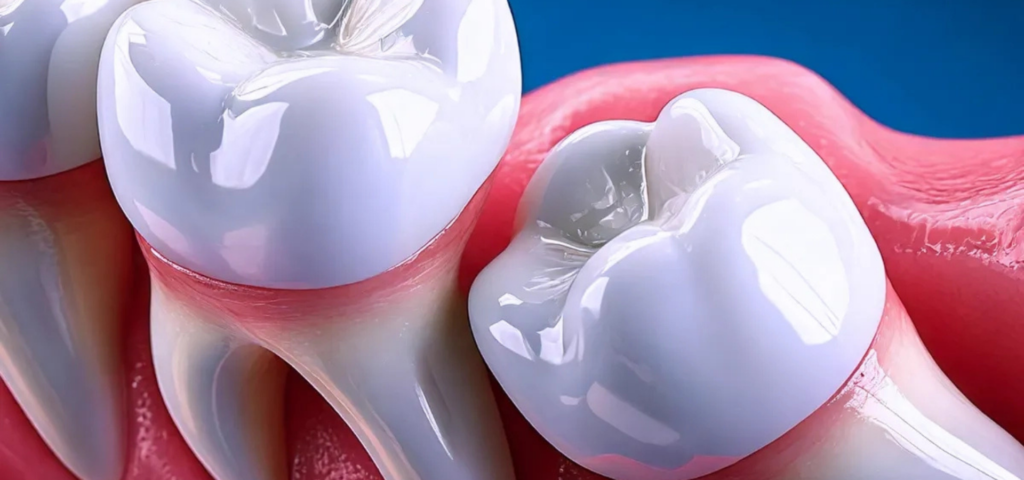

Restoratif Diş Hekimliği

Konservatif Diş Hekimliği